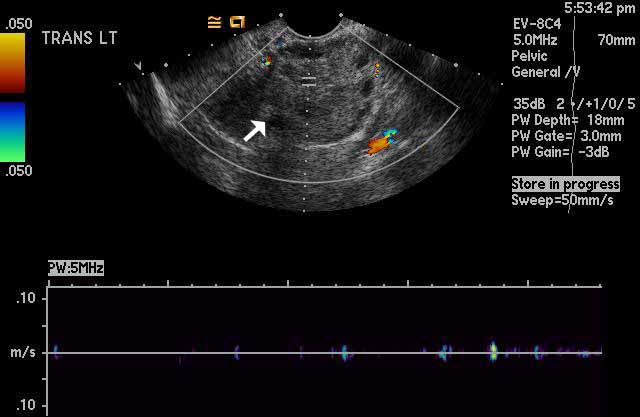

Image 2

Left ovarian torsion. Color Doppler ultrasound imaging shows absence of normal intra-ovarian color flow in the left ovary, white arrow, which indicates lack of vascularity and presence of torsion. The graph at the bottom of the image shows lack of normal Doppler waveform tracings, again indicating torsion. |